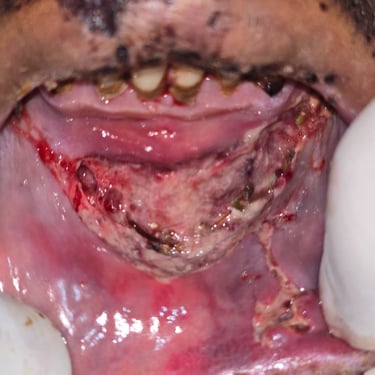

Restore facial harmony and function with advanced face reconstruction surgery. Our expert surgeons specialize in correcting trauma, birth defects, and post-tumor resection deformities to help you regain confidence and natural appearance.